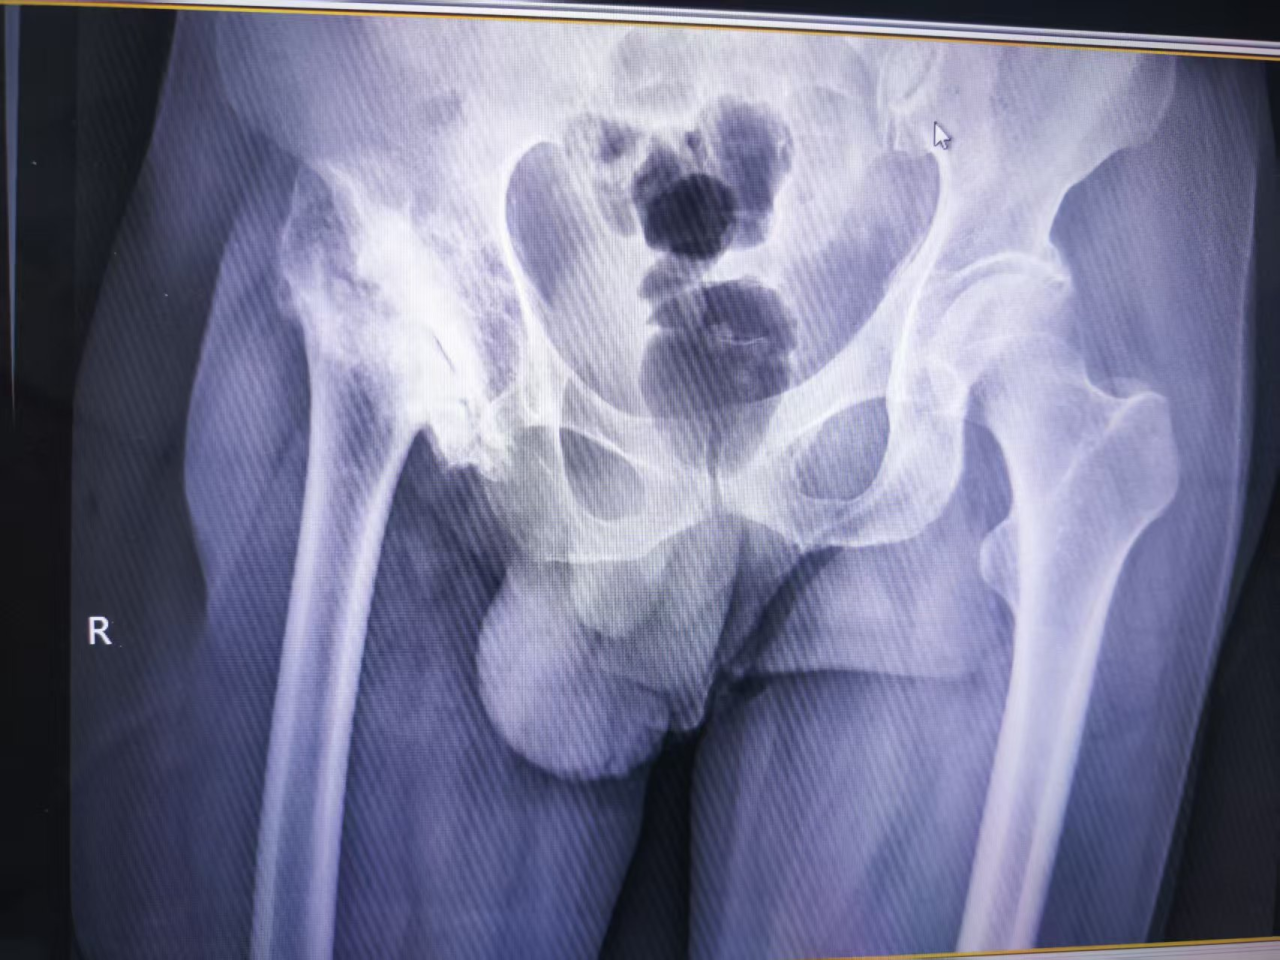

检查发现,种先生髋关节股骨头缺失,大结节严重上移,肌肉紧绷,关节结构紊乱,手术难度极大。

一是精准“画图”:运用3D技术还原髋关节模型,术前模拟手术,预判状况。

二是巧解难题:精准术前设计,重塑髋关节,下移大结节恢复力学平衡。